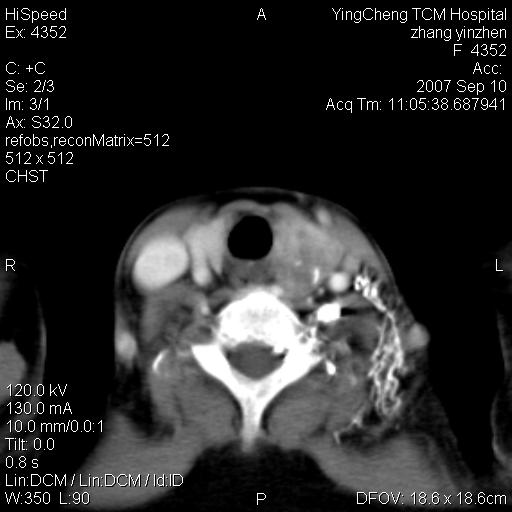

以下是引用卜一在2007-9-18 14:41:00的发言:[br]右肺肿块:毛刺+胸膜凹陷征+供血血管+浅分叶+强化。支持:周围性肺癌 !另:左侧甲状腺腺瘤!

以下是引用夏季在2007-9-18 11:00:00的发言:[br]1。右肺肿块,周围有短毛刺,肺门侧有血管与其相连,胸壁侧有胸膜凹陷征,考虑周围性肺癌 2。左侧甲状腺软组织肿块,内有高密度钙化灶,考虑左侧甲状腺腺瘤。